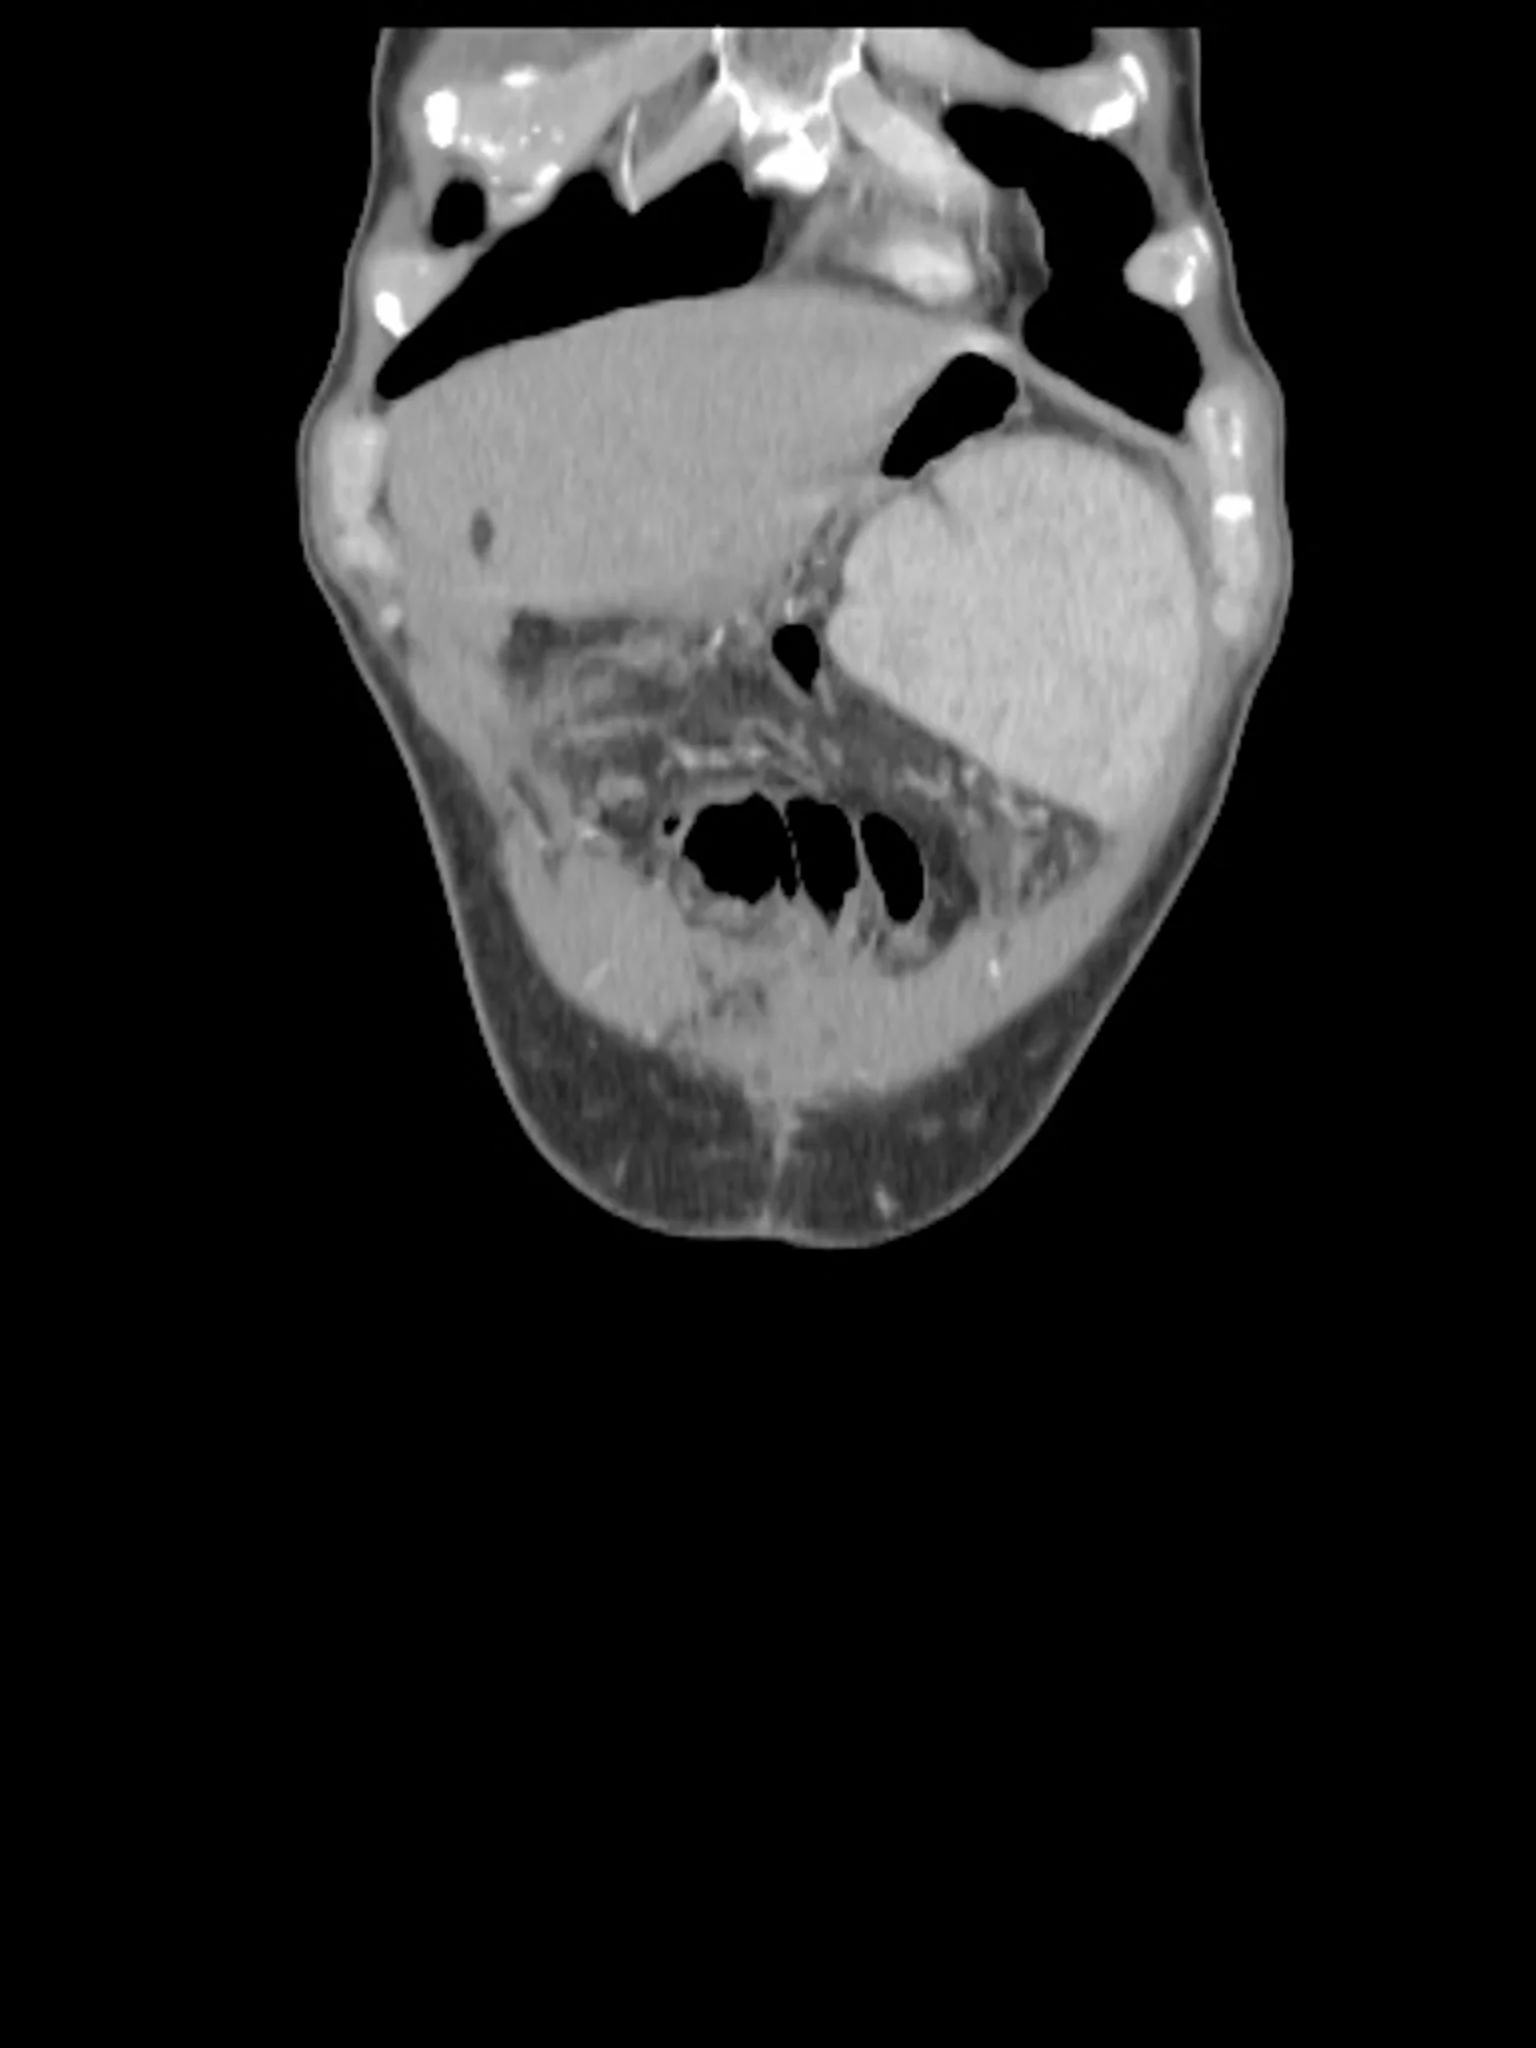

Around 10 million people worldwide live with Crohn’s Disease or Ulcerative Colitis — chronic, autoimmune conditions that affect the digestive system but leave scars everywhere: in the body, the mind, and human connections.

Those affected face shifting symptoms: pain, fatigue, malnutrition, chronic diarrhea, fever, and others.

On top of that come surgeries, invasive tests, evasive conversations with doctors. For life.